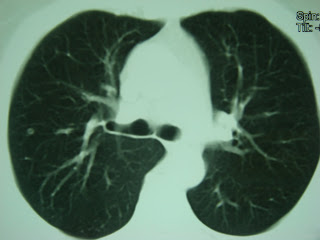

Metástases pulmonares bilaterais - neoplasia de cólon / Bilateral lung metastases - colon neoplasm

Marcadores: colon cancer, colon neoplasm, Lung, metastases, metástases, metástases pulmonares, pulmão, pulmonary metastasis